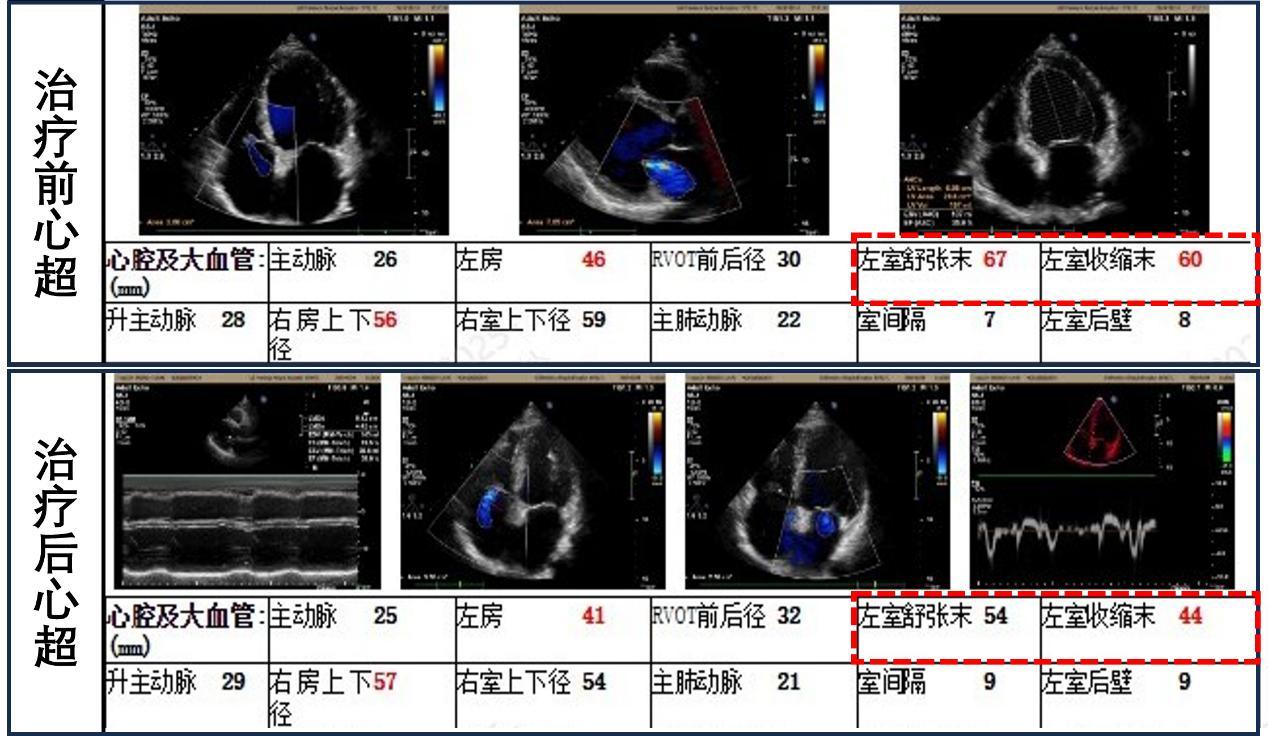

“心脏更强韧,肿瘤也在退缩。”金浩生教授介绍。此时,林大叔虽然核心的“泵血”功能指标(射血分数)提升有限,但显著的变化是,他那过度扩大的左心室明显缩小了——从60mm回缩至接近正常的44mm!这意味着心脏负担减轻,耐受手术的能力大大增强。